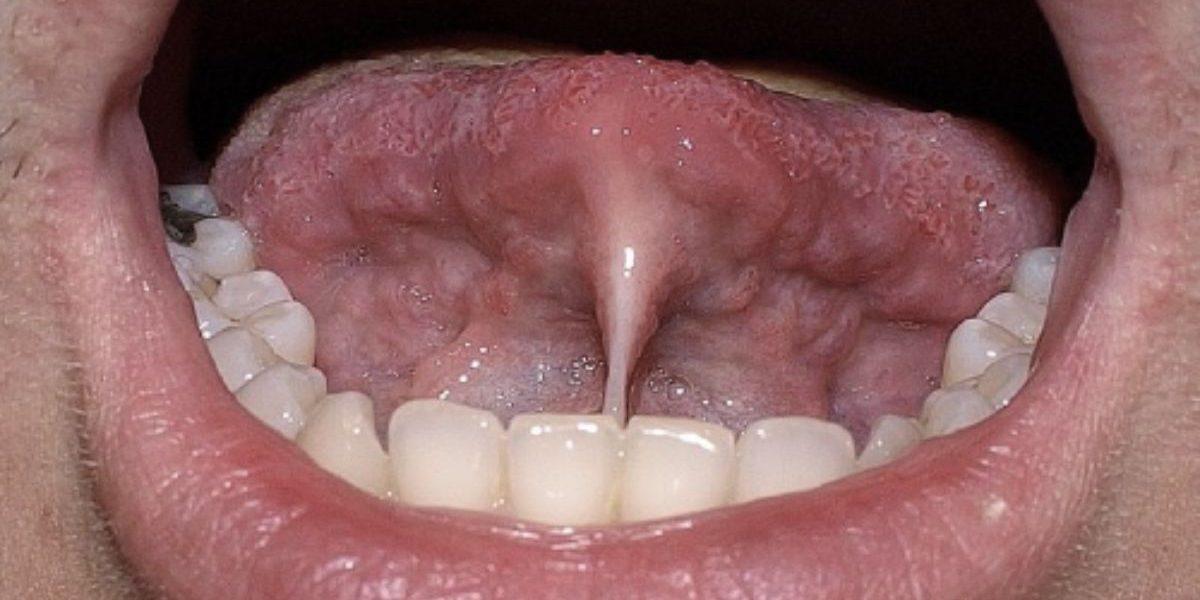

- Frenillo Lingual

Este tejido conecta la lengua al suelo de la boca, facilitando las actividades orofaciales, como la succión, deglución, masticación, y el habla.

Cuando este frenillo presenta una longitud reducida, se restringe la movilidad lingual, una condición conocida como anquiloglosia, pudiendo interferir con la lactancia en neonatos, afectar la ingesta nutricional, y ocasionar problemas de articulación fonética en niños más grandes.

Además, puede generar dificultades en la higiene oral y, a largo plazo, patologías dentales y periodontales.